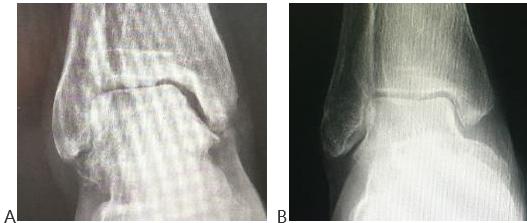

■ 图B:同样是50多岁的踝关节。正常健康的踝关节结构,关节间隙对称,无痛,活动自如,力线正常,良好负重。